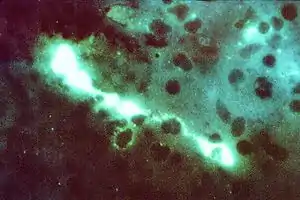

Direct fluorescent antibody

A direct fluorescent antibody (DFA or dFA), also known as "direct immunofluorescence",[1] is an antibody that has been tagged in a direct fluorescent antibody test. Its name derives from the fact that it directly tests the presence of an antigen with the tagged antibody, unlike western blotting, which uses an indirect method of detection, where the primary antibody binds the target antigen, with a secondary antibody directed against the primary, and a tag attached to the secondary antibody.

Commercial DFA testing kits are available, which contain fluorescently labelled antibodies, designed to specifically target unique antigens present in the bacteria or virus, but not present in mammals (Eukaryotes). This technique can be used to quickly determine if a subject has a specific viral or bacterial infection.

As with all types of fluorescence microscopy, the correct absorption wavelength needs to be determined in order to excite the fluorophore tag attached to the antibody, and detect the fluorescence given off, which indicates which cells are positive for the presence of the virus or bacteria being detected.